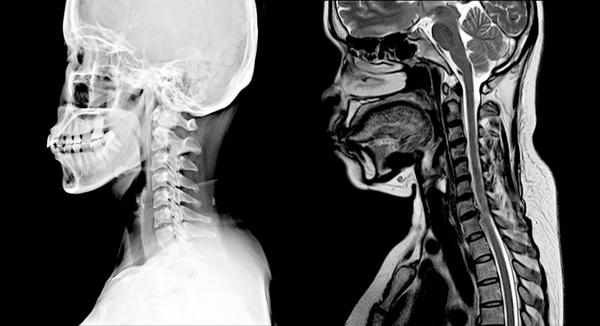

When you’re dealing with numbness, tingling, shooting pain, weakness, or stubborn neck/low back issues, the right imaging can change everything. An MRI can help us:

See disc bulges, herniations, stenosis, and nerve compression that X-rays can’t show.